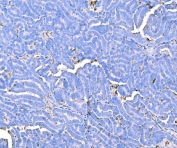

Prothrombin Antibody / Coagulation factor II / F2 [clone ACBD-6] (RQ4845)

Image RQ4845 Antibody in PBS with 0.02% sodium azide, 50% glycerol and 0.4-0.5mg/ml BSA 100 ul 439

Western blot testing with Prothrombin antibody. Predicted molecular weight ~70 kDa but may be observed at higher molecular weights due to glycosylation.